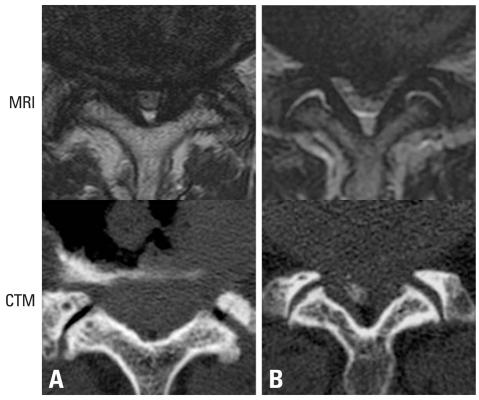

A comparison of MRI and computed tomography-myelography (CTM) for lumbar intracanalar dimensions. To compare the capability and reproducibility of MRI and CTM in measuring the cross-sectional morphology of intracanalar lesions of the lumbar spine.

MRI and CTM of lumbar disc levels from 61 subjects with various lumbar spinal diseases were studied. Dural area, dural anteroposterior (AP) diameter, dural right-left diameter, and thickness of the ligamentum flavum were measured by two orthopedic surgeons. Each section was graded by degree of stenosis. Absolute value and intra- and inter-observer correlation coefficients (ICC) of these measurements and the associations between MRI and CTM values were determined.

Except for MRI determination of ligament flavum thickness, CTM and MRI and intra- and ICC suggested sufficient reproducibility. When measurements of dural area, dural AP diameter, and RL diameter were compared, values in CTM were significantly (p = 0.01-0.004) larger than those in MRI (CTM/MRI ratios, 119%, 111%, and 105%, respectively). As spinal stenosis became more severe, discrepancies between CTM and MRI in measurements of the dural sac became larger.

Both CTM and MRI provided reproducible measurements of lumbar intracanalar dimensions. However, flavum thickness may be more accurately measured by CTM. Because the differences in the measurements between CTM and MRI are very slight and there is very little data to suggest that the precise degree of stenosis is related to symptoms or treatment outcome, the usefulness of the CTM over MRI needs to be confirmed in future studies.